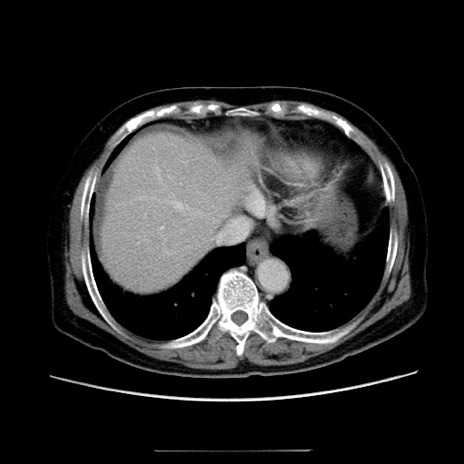

症例5(横断像)

【症例】70歳代女性

【主訴】お腹が張る

【現病歴】1週間くらい前から腹部膨満の自覚あり。昨日夜から増悪したため、本日救急外来受診。

【身体所見】意識清明、BT 36.5℃、BP 165/106mmHg、HR 80bpm、SpO2 98%、腹部:膨満、軟、自発痛・圧痛なし、触診にて不快感あり、腸蠕動音:減弱

【データ】WBC 12600、CRP 1.04